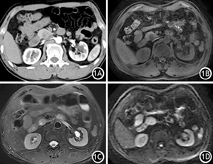

患者男性,63岁。以"腹胀伴腹痛半月"入院。半月前饭后出现上腹部腹胀伴腹痛,疼痛明显,呈持续性,无恶心呕吐,无发热寒战,无黑便腹泻。实验室检查:CAl25、CAl9-9、CEA、IgG4、淀粉酶均正常。腹部超声示胰腺头部低回声团块,边界尚清。上腹部增强CT示胰腺钩突部不均匀低密度肿块,约21 mm×18 mm,边界清楚,动脉期轻度强化,静脉期及延迟期呈明显强化,内部可见斑片状无强化区域(图1)。上腹部MR示胰腺钩突部团块状异常信号影,约21 mm×18 mm,病灶呈稍长T1、稍长T2信号,DWI呈稍高信号,内见斑片状长T1、长T2信号影(图1)。增强扫描见病变呈明显延迟强化,病灶与主胰管不相通。初步诊断:胰腺钩突神经内分泌肿瘤。1周后行胰头十二指肠切除术。切除的胰腺标本剖开后见大小20 mm×16 mm×16 mm肿物,切面呈灰白色,质韧,与周围分界清楚,有包膜。镜下见病灶由分化良好的腺泡及排列紊乱的导管构成,周围见纤维间质(图2)。免疫组织化学染色结果:CK7(+),CD56(-),CgA(-),Syn(-),Ki-67(+<5%),CK19(+)(图2)。病理诊断为胰腺错构瘤。术后随访6个月,患者恢复良好,无复发迹象。

胰腺错构瘤最常见于胰腺头部,但也见于体部和尾部。影像学表现无特异性,CT多表现为边界清楚的等密度或低密度团块,部分内部可见脂肪密度[7]。MR可见病变为长T1、长T2信号,常伴有囊性改变,DWI像呈等或高信号[2,8]。延迟期强化是其显著特点[2,6,9,10],这种强化方式可能与病变中含有较多纤维成分有关。胰头部较大的错构瘤可引起胰管受压导致远端胰管扩张[8,9,10]。18F-FDG PET显示病变为正常代谢[2,4]。胰腺错构瘤的影像学表现需要与胰腺癌、神经内分泌肿瘤及实性假乳头状瘤相鉴别。胰腺癌以胰头部多见,多伴有胰腺体尾部萎缩及主胰管扩张,容易侵犯周围结构并发生远处转移。胰腺癌为乏血供病变,增强扫描见轻度不均匀强化,强化程度低于胰腺实质;胰腺神经内分泌肿瘤多为富血供肿瘤,增强扫描动脉期明显强化,延迟期强化程度与胰腺实质相似,然而部分高级别神经内分泌肿瘤在动脉期呈轻度强化,静脉期及延迟期强化程度升高,与胰腺错构瘤鉴别困难。胰腺实性假乳头状瘤好发于年轻女性,边界清楚,有完整包膜,多为囊实性肿块,囊性成分与实性成分相间分布,实性成分似漂浮在囊性成分中,即"浮云征",增强扫描可见轻中度延迟强化,可伴有出血及钙化。